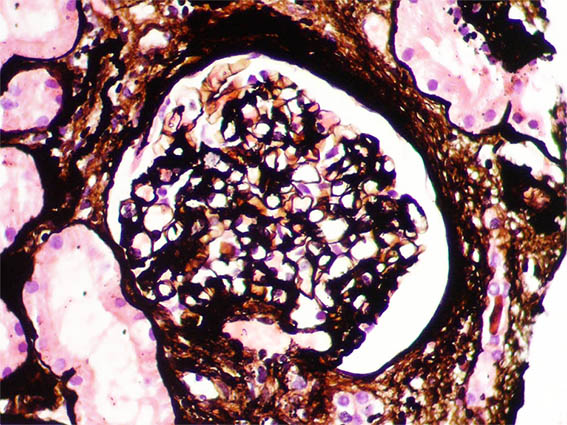

Figura 1. Tricrómico de Masson, X400. Glomérulos normales; hay fibrosis periglomerular.

Figura 2. Plata-metenamina, X400. Glomérulo con características normales.